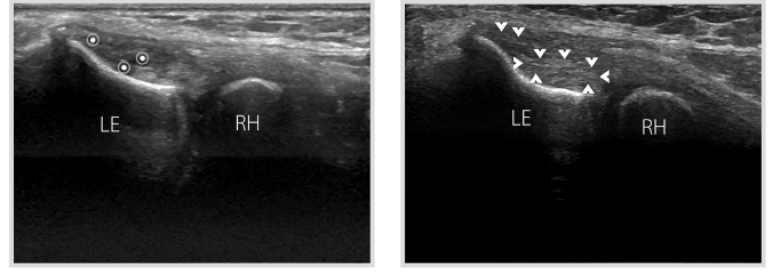

급성기에는

혈관 증식이 나타나기도 하고,

도플러 검사에서 혈류 시그널이 증가되어 있습니다.

만성기에는

힘줄이 붙어있는 뼈가

가시처럼 자라나기도 합니다.

(골극, Spur)

힘줄의 만성적 긴장으로 골막이 당겨지고, 조골세포가 이동하면서 뼈가 가시처럼 자라나게 됩니다. (Spur) @근막경선해부학

전기침 치료 후, 회복된 힘줄